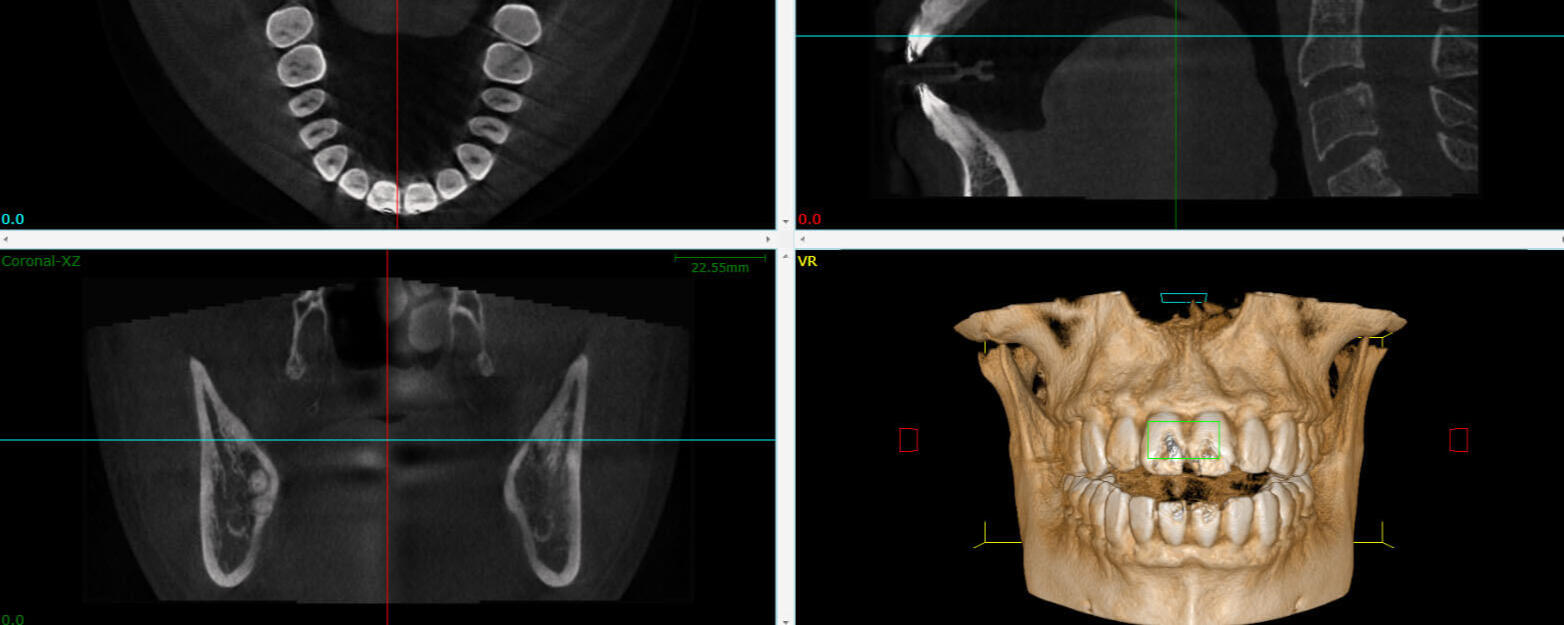

Tomografía 3D con CBCT (Cone Beam Computed Tomography)

Somos una clínica dental especializada en imágenes 3D, dedicada a brindar diagnósticos precisos y tratamientos personalizados. Nuestro equipo profesional combina experiencia, ética y calidez humana para ofrecer atención clara, eficiente y confiable. Creemos que la tecnología avanzada debe ir de la mano con un trato empático y transparente.